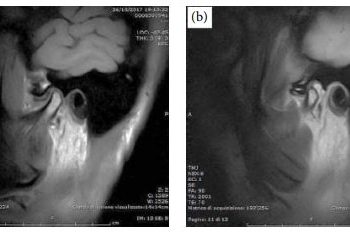

I medici dell’ospedale Ca’ Foncello hanno salvato la vista ad un ragazzo che ha fatto esplodere un proiettile trovato in strada. Una frammento del proiettile di una scacciacani gli si era conficcato a pochi millimetri dal bulbo oculare.